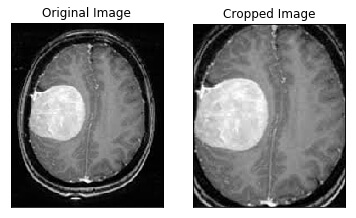

def crop_brain_contour(image, plot=False):

# Convert the image to grayscale, and blur it slightly

gray = cv2.cvtColor(image, cv2.COLOR_BGR2GRAY)

gray = cv2.GaussianBlur(gray, (5, 5), 0)

# Threshold the image, then perform a series of erosions +

# dilations to remove any small regions of noise

thresh = cv2.threshold(gray, 45, 255, cv2.THRESH_BINARY)[1]

thresh = cv2.erode(thresh, None, iterations=2)

thresh = cv2.dilate(thresh, None, iterations=2)

# Find contours in thresholded image, then grab the largest one

cnts = cv2.findContours(thresh.copy(), cv2.RETR_EXTERNAL, cv2.CHAIN_APPROX_SIMPLE)

cnts = imutils.grab_contours(cnts)

c = max(cnts, key=cv2.contourArea)

# Find the extreme points

extLeft = tuple(c[c[:, :, 0].argmin()][0])

extRight = tuple(c[c[:, :, 0].argmax()][0])

extTop = tuple(c[c[:, :, 1].argmin()][0])

extBot = tuple(c[c[:, :, 1].argmax()][0])

# crop new image out of the original image using the four extreme points (left, right, top, bottom)

new_image = image[extTop[1]:extBot[1], extLeft[0]:extRight[0]]

if plot:

plt.figure()

plt.subplot(1, 2, 1)

plt.imshow(image)

plt.tick_params(axis='both', which='both',

top=False, bottom=False, left=False, right=False,

labelbottom=False, labeltop=False, labelleft=False, labelright=False)

plt.title('Original Image')

plt.subplot(1, 2, 2)

plt.imshow(new_image)

plt.title('Cropped Image')

plt.show()

return new_image

In [3]:

ex_img = cv2.imread('yes/Y1.jpg')

ex_new_img = crop_brain_contour(ex_img, True)